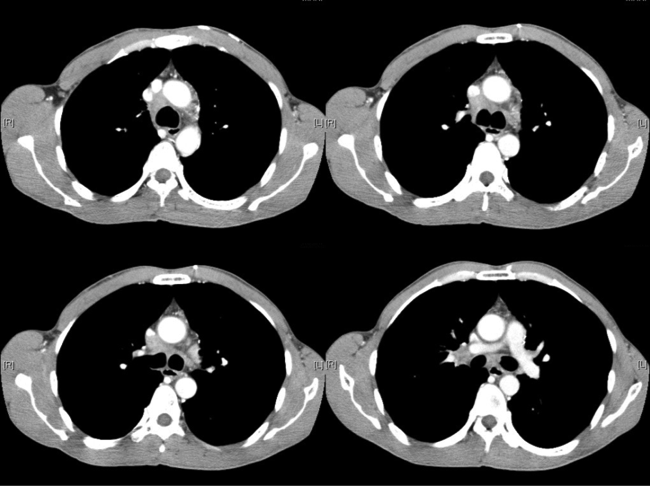

The patient was a chronic smoker (30 pack-years) and chronic drinker. He was a construction site worker and his past health was good. He presented with headache for a few weeks and was found to have signs of superior vena cava obstruction (SVCO). He did not have other complaint and the rest of the physical examination was normal. His CXR was unremarkable (Fig 4). His plain CT brain was also unremarkable. His initial blood tests including complete blood picture, renal & liver function test, erythrocyte sedimentation rate, urate, lactate dehydrogenase and tumor markers (including carcinoembryonic antigen, alpha-fetoprotein and prostate-specific antigen) were normal. His sputum was negative for culture, acid fast bacilli and cytology. His contrast CT thorax showed enlarged lymph nodes (LN) in the right lower paratracheal, pre-carinal & right hilar region and aorto-pulmonary window. The enlarged right lower paratracheal and precarinal LN compressed the brachiocephalic veins and superior vena cava (Fig 5). FOB with transbronchial needle aspiration under endobronchial ultrasound guidance (EBUS-TBNA) were done. The specimen of the right lower paratracheal LN was reported as suboptimal while the specimen from the right hilar LN was negative for any significant pathology. In view of SVCO was a potential medical emergency, we suggested surgical biopsy of the mediastinal LNs to ascertain their nature more definitively in order to guide subsequent management. He was then referred to the thoracic surgery clinic and PET-CT was done as suggested by the thoracic surgeon. The PET-CT was reported as “There were multiple enlarged hyper-metabolic mediastinal LNs (SUVmax 3.3-6.5) and the provisional diagnosis would include lymphoproliferative disease.” A hypermetabolic focus (1.7cm x 1.0cm x 2.3cm, SUVmax = 4.7) in the periphery of the right vastus lateralis muscle was also found incidentally (Fig 6A, 6B). At that juncture, the working diagnosis was SVCO due to possible lung carcinoma with LN metastases or lymphoma. The right thigh lesion could be part of the disease or something unrelated. Right anterior mediastinotomy and biopsy of the right lower paratracheal LN were done. Histology showed a piece of fibrous tissue with marked suppurative granulomatous inflammation. However, infective stains including Ziehl-Neelsen (ZN) stain were negative. His tuberculin skin test was 24mm (that was strongly positive) and his histoplasma antibody was negative. Standard anti-tuberculosis (TB) treatment was started and the signs of SVCO resolved progressively. Later, ultrasound guided FNA of his right thigh lesion showed granulomatous inflammation and one acid fast bacillus. Thus the final diagnosis was TB mediastinal lymphadenopathies causing SVCO, and right thigh TB infection. An interval CT about four months after anti-TB treatment showed the mediastinal LNs were decreased in size.

Figure 5